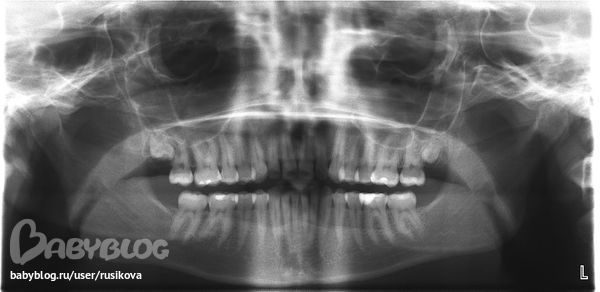

И про мои зубки очень мучает вопрос про зубы мудрости они прорезались у меня недавно мне 27 лет нижние зубы накрыты десной.Это вызывет дискомфорт.Ходила в поликлинику при прорезывании делали только горизонтальный надрез, но зуб по краям так и остался в десне.Что делать хорошо почистить его не получается.И такое ощущение что эти зубы стоматологи сразу готовы удалить.Они что не нужные?Еще кровоточат десны.Что может помочь?У меня ребенок на ГВ.Может нужно принимать какие то препараты чтобы зубы не испортились.Ведь сейчас столько нужно кальция.